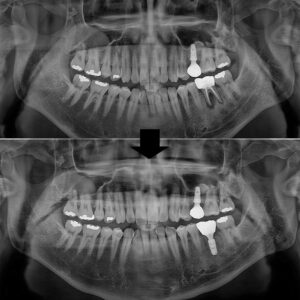

파노라마 사진을 살펴보면

유독 치아 뿌리쪽이 까맣게

보이는 부분을 보실 수 있는데요.

이는 염증으로 인해

잇몸뼈가 녹아 있는 모습이에요. 😥

이미 신경치료가 되어 있는 치아였지만

또 다시 염증이 발생하여

잇몸뼈를 상당히 녹인 상태였어요.

염증으로 인한 잇몸뼈의 소실로

치아의 흔들림이 있는 현재 상태에서는

치아를 살려 사용하기 어렵다고 판단되었어요.👨⚕️

그래서 발치 후 당일임플란트를

식립하기로 하였고,

잇몸뼈가 녹아 비어있는 부분은

뼈이식을 함께 진행하기로 하였어요.❗

식립 전, 후 사진을 비교해 볼게요.

뼈이식이 된 부분은 발치 전과 달리

하얗게 보이는 모습을 볼 수 있어요.